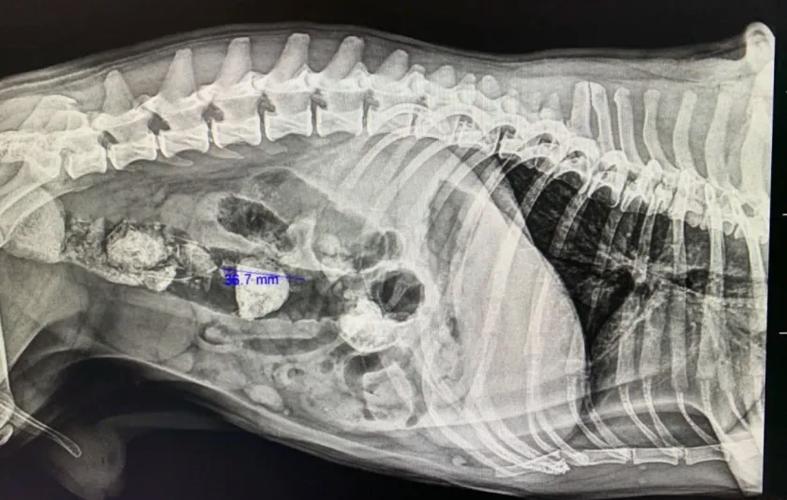

狗狗胃下面的肠子里有东西卡住怎么办?去检查拍片子医生说有东西在里面...

如果您的狗狗不慎吞食了异物,且异物卡在了肠子里,应立即前往宠物医院进行X光检查。 如果异物较小,医生可能会建议喂食一些化毛膏或者富含油脂的食物,这些有助于异物通过肠道排出。 同时,可以给狗狗喂食一些肠胃宝等益生菌,以保护肠胃健康并促进肠胃蠕动。

如果是误食了异物,卡在肠道里了,就要尽早去医院拍片检查,如果异物不大的话,可以喂些化毛膏或油脂大的食物,可以帮助异物排出,也可以把肠胃宝喂一下,能保护肠胃,促进肠胃蠕动。但如果异物较大,就只能尽早手术治疗了。

〖贰〗、以下是狗狗肠梗阻的治疗方法: 寻求兽医帮助:如果怀疑狗狗患有肠梗阻,应立即带它去兽医那里就诊。 诊断确认:兽医可能会进行体格检查、触诊和X光等检查,以确定是否为肠梗阻。根据严重程度,可能还需要进行超声波或其他进一步检查。

〖叁〗、如果你怀疑狗狗有肠梗阻,请立即采取行动。 立即就医:带狗狗去兽医诊所或紧急救治中心。专业兽医会进行体检和必要的检查,如X光或超声波,以确定肠梗阻的位置和严重程度。 不要试图自行处理:肠梗阻需要专业医生的干预和治疗。不要尝试使用家庭疗法或药物来解决问题,这可能会加重狗狗的病情。